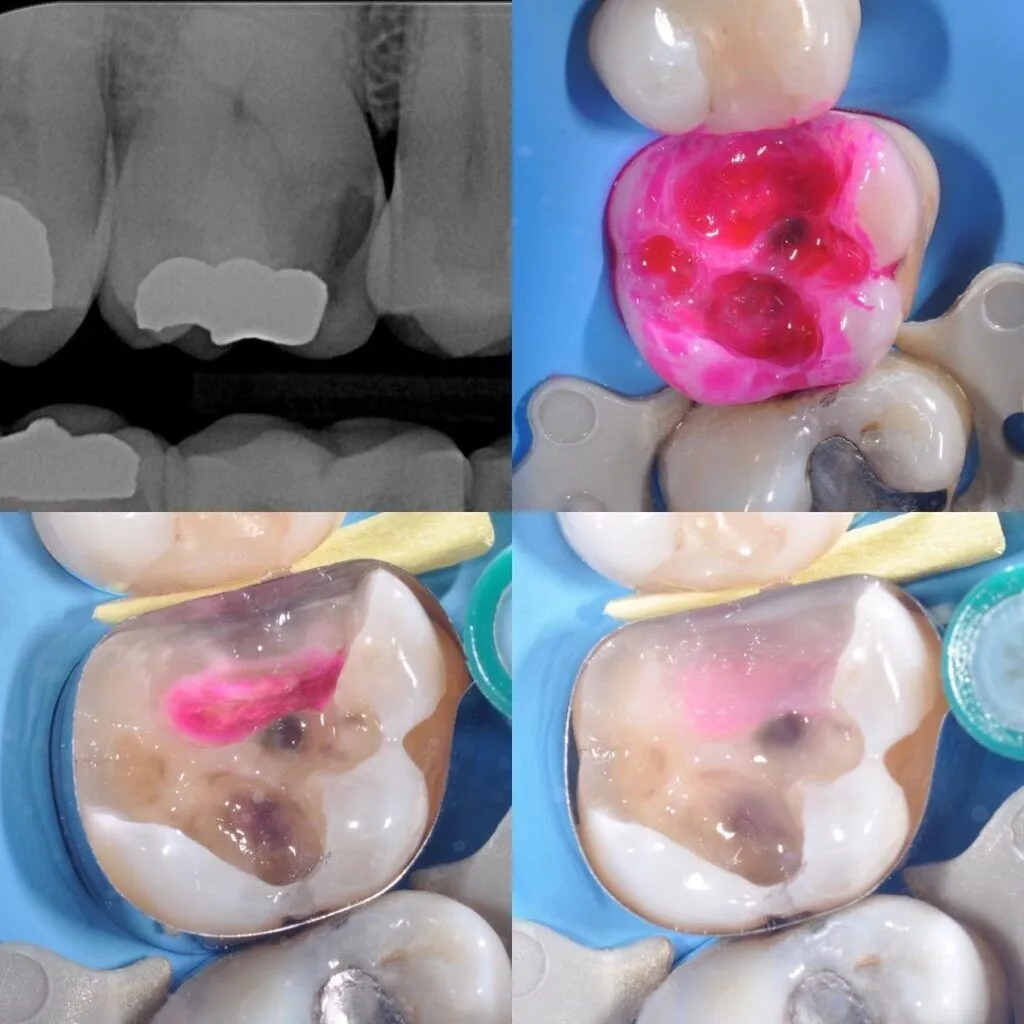

توضیحاتدای آشکار ساز پوسیدگی کبالت cobaltمحلول تشخیص پوسیدگی لایه ی سطحی از عاج پوسیده را رنگ کرده و از لایه ی زیرین عاج سالم و یا پوسیده متمایز میکند . این رنگ پذیری لایه ای باعث برداشت حداقلی از عاج پوسیده شده و به عنوان یک راهنمای مفید در برداشت پوسیدگی عمل میکند .این محصول فقط برای کاربرد دندانی طراحی شده استهنگام مصرف از دستکش استفاده شود و برای جلوگیری از واکنش حساسیت زایی از تماس مستقیم با دست جلوگیری کنیدپس از کار با محصول درب آن را ببندیدو از ورود رطوبت به بطری پیشگیری کنیدCobalt Caries Detector Dye – نشانگر پوسیدگی کبالتپوسیدگیهای دندانی در تمامی شکافها و منافذ سطح دندان جای میگیرند. به همین دلیل تشخیص دقیق محل پوسیدگیها روی سطح دندان کار بسیار مشکلی است. گاهی اوقات ممکن است دندانپزشک از آینه دندانپزشکی برای مشاهدۀ پوسیدگیهایی که درون کانالهای دندانی قرار دارند استفاده کند. اما برخی از پوسیدگیها به حدی جزئی هستند که نمیتوان همه آنها را با چشم مسلح تشخیص داد.در این حالت باید از محصولی به نام نشانگر پوسیدگی استفاده کرد.نشانگر پوسیدگی کبالتیکی از بهترین محصولاتی است که در این زمینه به دندانپزشکان پیشنهاد میشود. آماده کردن این نشانگر پوسیدگی بسیار راحت است و به همین دلیل باعث هدر رفتن وقت دندانپزشک نخواهد شد. به کمک این محصول میتوان تمامی بخشهای دندان که مشاهدۀ پوسیدگی روی سطح آنها دشوار است را مشاهده کرد.ویژگی های نشانگر پوسیدگی دندان کبالتاین نشانگر مقدار دقیق و جزئی پوسیدگیها را نشان میدهد. در نتیجه از برداشتن بیش از حد بخشهای داخلی کانال دندان جلوگیری خواهد کرد.نشانگر پوسیدگی کبالت در مواجهه با پوسیدگیها تغییر رنگ میدهد.بسته بندی نشانگر پوسیدگی کبالت شامل 6 میل مایع و یک عدد سرنگ است.نشانگر پوسیدگی دندان کبالتهمچنین از بروز خطای چشم جلوگیری میکند و یک محصول کاملاً متمایز و عالی برای مشاهدۀ پوسیدگیهای دندانی است.